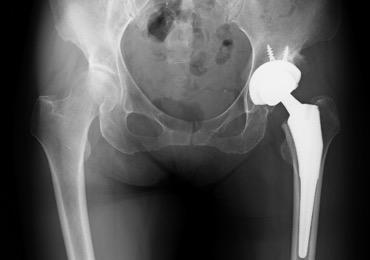

人工股関節全置換術(THA)

人工股関節全置換術とは、すり減った軟骨と痛んだ骨を取り除き、金属やプラスチックでできた人工の関節に置き換える手術です。

痛みの原因を除去できるため、確実な除痛効果が得られます。長期的にも、人工股関節全置換術施行後、10年で再置換術が必要となる確率は5%以下であり、多くの方が10年後も良好な機能を保ちつつ生活されております。

当院では、変形の程度によりますが、最小侵襲手術手技を採用し、かつ長期的な成績改善を第一優先として正確なインプラント設置を行っております。術直後の痛みは、麻酔科の協力により良好にコントロールされます。リハビリは術翌日より開始し、日常生活の復帰や社会復帰へ向け準備致します。主な術後合併症である感染と脱臼の発生率は、一般に約1-2%と5%前後ですが、当院では現在筋肉を切らない手術(MIS)を採用しており、その率は非常に低く抑えられています。

従来、人工股関節全置換術は、15cm~20cmの皮膚切開を要し、筋肉を切開して関節に達しておりました。近年、手術手技や手術機械の飛躍的な進歩によりMIS手術が導入され、10cm~12cmの皮膚切開で、かつ筋肉同士の間からアプローチするため筋肉をほぼ切らずに従来と同等の人工股関節置換術が可能となりました。当院では十分にトレーニングを積んだ専門医が適応を十分に判断した上で、積極的にMIS手術を取り入れており、術後早期の回復及び脱臼率の低下などの成果が上がっています。

![]() 人工股関節全置換術後のレントゲン |